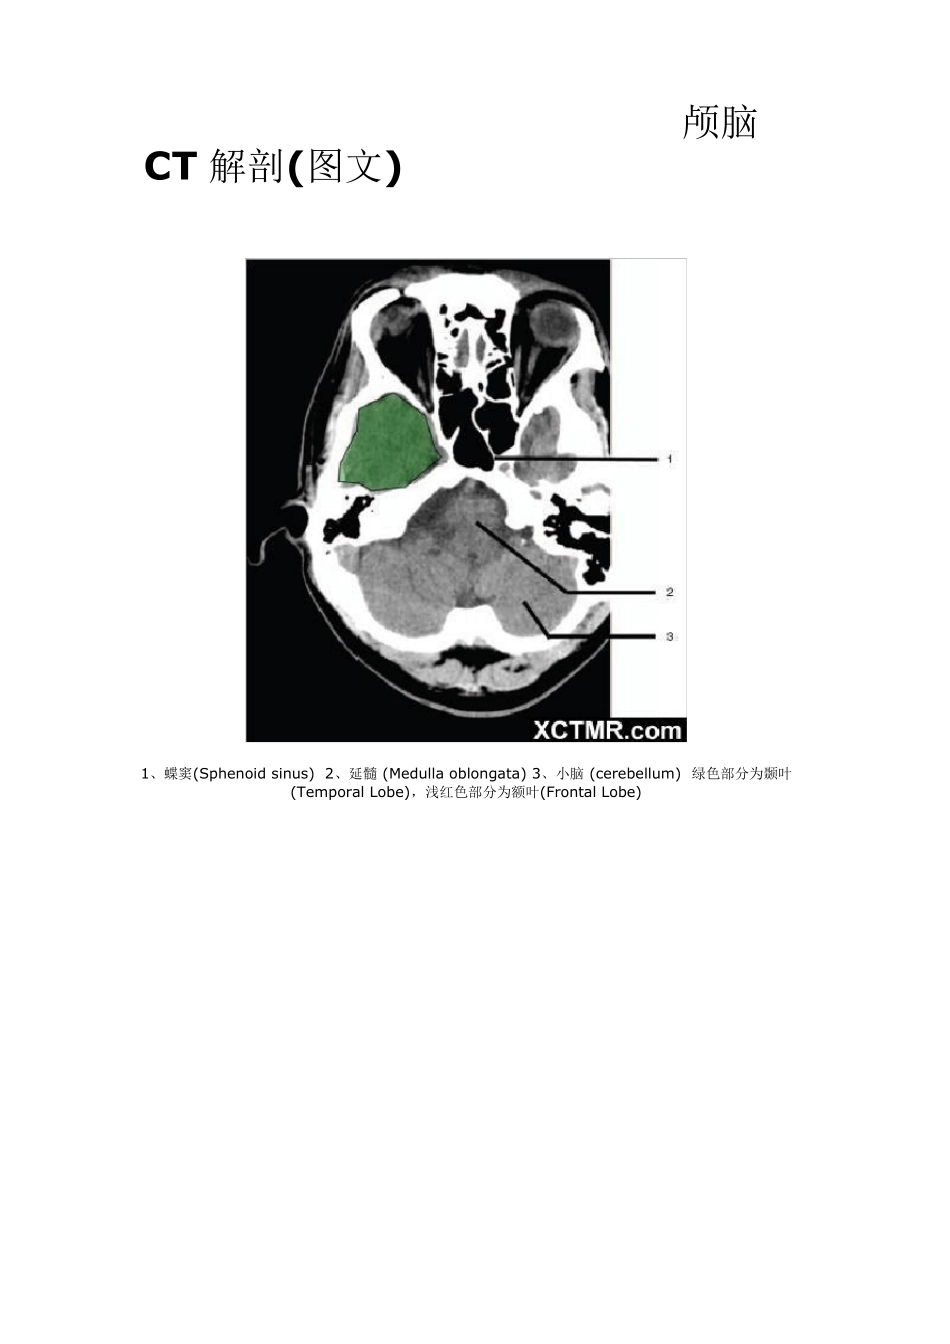

颅脑CT 解剖(图文) 1、蝶窦(Sphenoid sinu s) 2、延髓 (Medu lla oblongata) 3、小脑 (cerebellu m) 绿色部分为颞叶(Temporal Lobe),浅红色部分为额叶(Frontal Lobe) 4、第四脑室(Fourth ventricle) 5、小脑中角(Middle cerebellar peduncle) 6、乙状窦(Sigmoid sinus) 7、颞骨及乳突气房 (Petrous temporal bone and mastoid air cells) 8、桥小脑角(Cerebellopontine angle) 9、脑桥 (Pons) 10、垂体窝(Pituitary fossa) 绿色部分为颞叶(Temporal Lobe),浅红色部分为额叶(Frontal Lobe) 11、小脑蚓部(Cerebellar vermis) 12、基底动脉(Basilar artery) 13、桥前池 (Prepontine cistern) 14、鞍背 (Dorsum sellae) 15、侧脑室颞角(Temporal horn of lateral ventricle) 绿色部分为颞叶(Temporal Lobe) ,浅红色部分为额叶(Frontal Lobe) 16、环池 (Ambient cistern) 17、角间池 (Interpeduncular cistern) 18、大脑角 (Cerebral peduncle) 19、侧裂池 (Sylvian fissure) 绿色部分为颞叶(Temporal Lobe),浅红色部分为额叶(Frontal Lobe) 20、小脑上池 (Third v entricle) 21、侧脑室前角 (Frontal horn of lateral v entricle) 21a、第三脑室 (Third v entricle) 绿色部分为颞叶(Temporal Lobe),浅红色部分为额叶(Frontal Lobe),黄色部分为枕叶(Occipital Lobe) 22、尾状核头部 (Head of caudate nucleus) 23、岛叶 (Insular cortex) 24、外囊 (External capsule) 25、豆状核(Lentiform nucleus) 26、丘脑(Thalamus) 绿色部分为颞叶(Temporal Lobe),浅红色部分为额叶(Frontal Lobe),黄色部分为枕叶(Occipital Lobe) 27、纵裂 (Interhemispheric fissure) 28、内囊前肢 (Anterior limb of internal capsule) 29、内囊膝部 (Genu of internal capsule) 30、内囊后肢(Posterior limb of internal capsule) 31、侧脑室三角区及脉络丛钙化(Trigone of lateral ventricle and calcified choroid plexus) 32、侧脑室枕角(Occipital horn of lateral ventricle) 绿色部分为颞叶(Temporal Lobe),浅红色部分为额叶(Frontal Lobe),黄色部分为枕叶(Occipital Lobe),褐色部分为顶叶(Parietal Lobe) 33、侧脑室体部 (Body of lateral ventricle) 34、放射冠 (Corona radiata) 浅红色部分为额叶(Frontal Lobe),黄色部分为枕叶(Occipital Lobe),褐色部分为顶叶(Parietal Lobe) 35、半卵圆中心 (Centrum semiovale) 浅红色部分为额叶(Frontal Lobe),黄色部分为枕叶(Occipital Lobe), 褐色部分为顶叶(Parietal Lobe) 额骨(FB— Frontal bone) 顶骨(PB — Parietal bone) 枕骨(OB— Occipital bone) 36、中央前回 (Pre-central gyrus) 37、中央沟(Central sulcus ) 38、中央后回 (Post-central gyrus) 浅红色部分为额叶(Frontal Lobe),褐色部分为顶叶(Parietal Lobe) 浅红色部分为额叶(Frontal Lobe),褐色部分为顶叶(Parietal Lobe) 浅红色部分为额叶(Frontal Lobe),褐色部分为顶叶(Parietal Lobe)